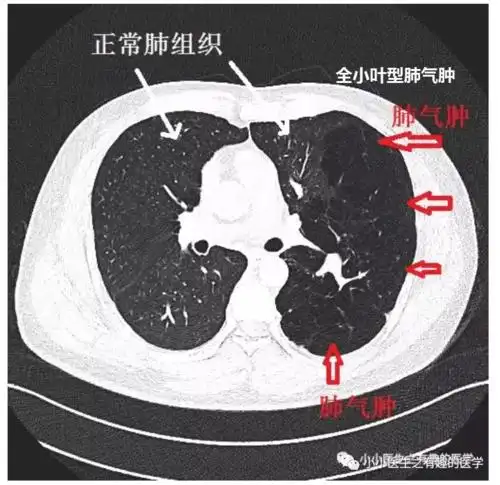

肺气肿ct典型图谱,一学就会_医学界-助力医生临床决策和职业成长

肺气肿的影像诊断

ct经典图谱:肺气肿拿不准?经典ct,3分钟学会